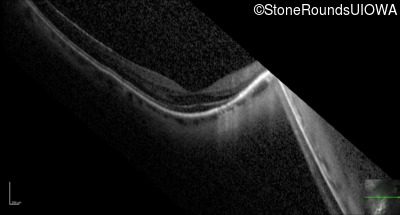

Optical Coherence Tomography - Left - 20/25 +2

Exemplar / OCT Stack